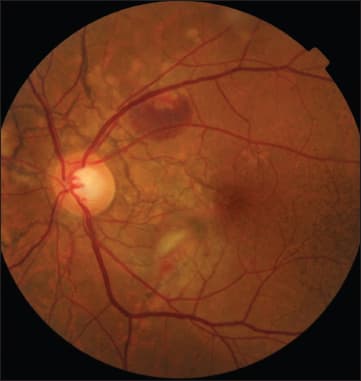

Figure 1a. The right eye showed features characteristic of angioid streaks.

A color photograph of the patient's right eye (Figure 1a) showed characteristic features of angioid streaks: irregular lines around the peripapillary area with intercommunicating branches. There was a subretinal hemorrhage, over which retinal blood vessels were crossing superionasal to the fovea; there was also a subretinal neovascular membrane that was approaching, but did not involve, the center of the macula. Also, we noticed RPE scarring around the disc and in the nasal macula as well.

Late-phase fluorescein angiography of the same eye (Figure 1b) showed the extent of these angioid streaks, with staining caused by subretinal scarring and a subretinal neovascular membrane within the superior macula.